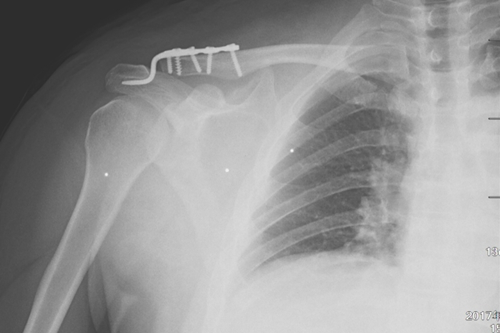

术前DR

一名50岁的男性患者,因不慎摔伤致右肩关节肿痛,并伴活动受限4天后来附院求治。入院查体发现患者右肩部肿胀明显,右锁骨远端隆起畸形,局部明显按压出现疼痛,肩部外展活动受限,进行X线检查显示“右肩锁关节脱位”。骨三科医师团队根据患者病情,进行充分商讨,确定了手术治疗方案,决定为患者实施“右肩锁关脱位复位带袢钢板内固定术”。由副主任医师蒋宇平主刀,骨三科手术团队在患者锁骨上方及喙突处各取2cm手术切口,将肩锁关节复位后,使用瞄准器由喙突基底部向锁骨远端建立骨性隧道,最后将带袢钢板由骨道穿出后固定,术中出血仅10ml左右。